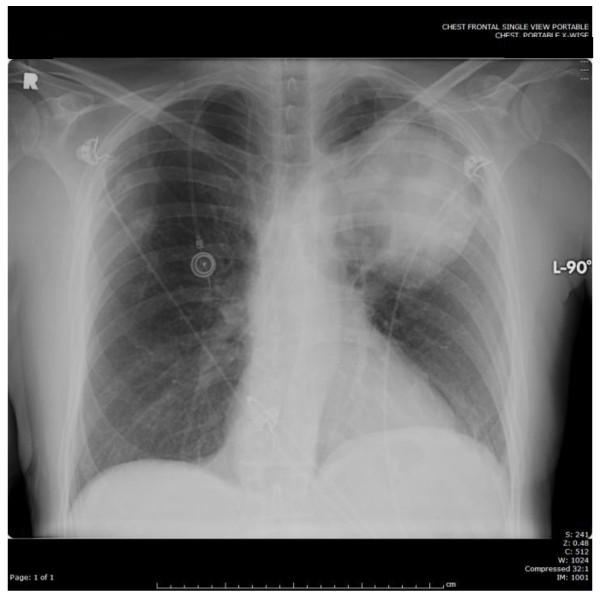

Extension of primary lung tumors into the left atrium via pulmonary veins is a well-documented phenomenon. Peripheral arterial embolism and cerebral embolism originating from a primary lung neoplasm are rare events. We report a case of simultaneous acute bilateral lower limb ischemia, bilateral renal infarction, splenic infarction and cerebral infarction as a result of multiple emboli originating from primary lung malignancy invasion of the left atrium. An emergent embolectomy revealed pathologic features of the extracted thrombus that were identical to the pulmonary neoplasm.

原发性肺肿瘤经肺静脉延伸至左心房是一种有充分文献记载的现象。源自原发性肺肿瘤的外周动脉栓塞和脑栓塞是罕见事件。我们报告一例因原发性肺恶性肿瘤侵犯左心房导致多发栓子形成,进而出现同时性急性双侧下肢缺血、双侧肾梗死、脾梗死和脑梗死的病例。急诊栓子切除术显示取出的血栓病理特征与肺肿瘤相同。